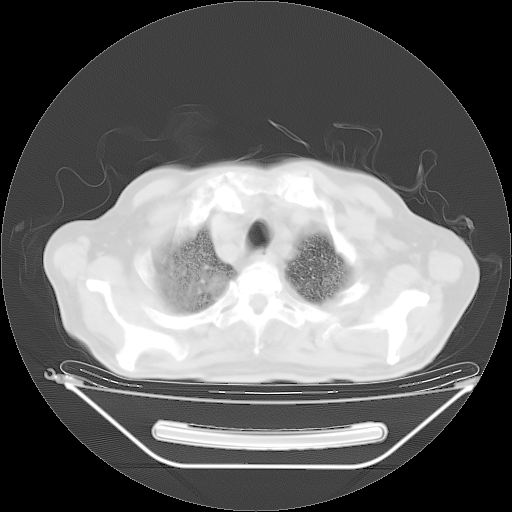

今天复查肺部CT,发现双肺广泛磨玻璃样改变。所以我把3月19日和5月9日相隔50天的肺部CT上传。请大家会诊。

5月9日肺部CT(在4月27日齐鲁医院肺部CT描述部分肺组织磨玻璃样改变,12天后肺组织广泛磨玻璃样改变)

2009年5月9日肺部CT